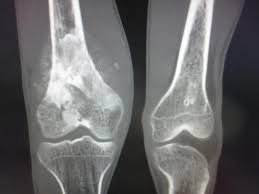

Jenis kanker yang terbentuk pada jaringan tulang dan termasuk dalam kategori kanker langka, namun kanker tulang gejala dan pemahamannya yang masih terbatas di masyarakat sehingga menjadi memiliki mitos seputar penyakit ini pun berkembang. Yuk memahami mana yang benar dan mana yang sekedar mitos sangat penting agar tidak salah kaprah dalam menyikapi kondisi ini.

Mitos 1 : kanker tulang hanya menyerang pada lansia

Faktanya : kanker tulang justru lebih sering ditemukan pada anak, remaja dan dewasa muda. Jenis kanker tulang primer seperti osteosarcoma paling banyak terjadi pada usia 10-30 tahun. Meski terjadi pada lansia yang dialami kanker tulang sekunder, yaitu kanker yang menyebar dari organ lain.